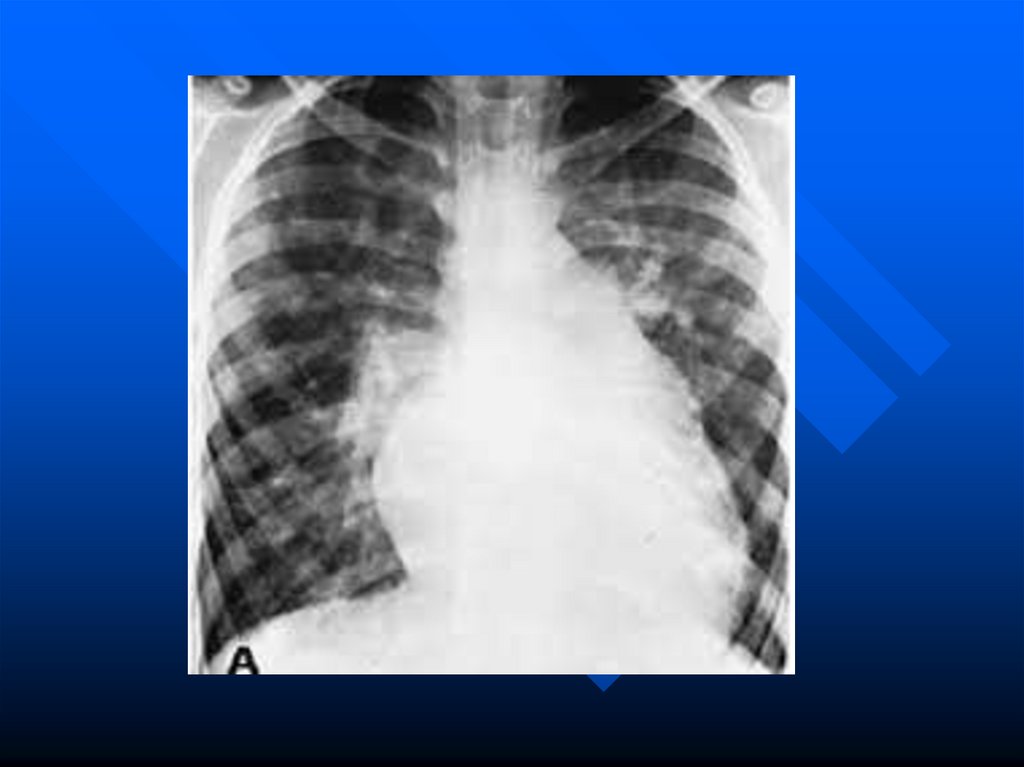

Структурное оформление сердца (оно

становится 4-камерным) и крупных